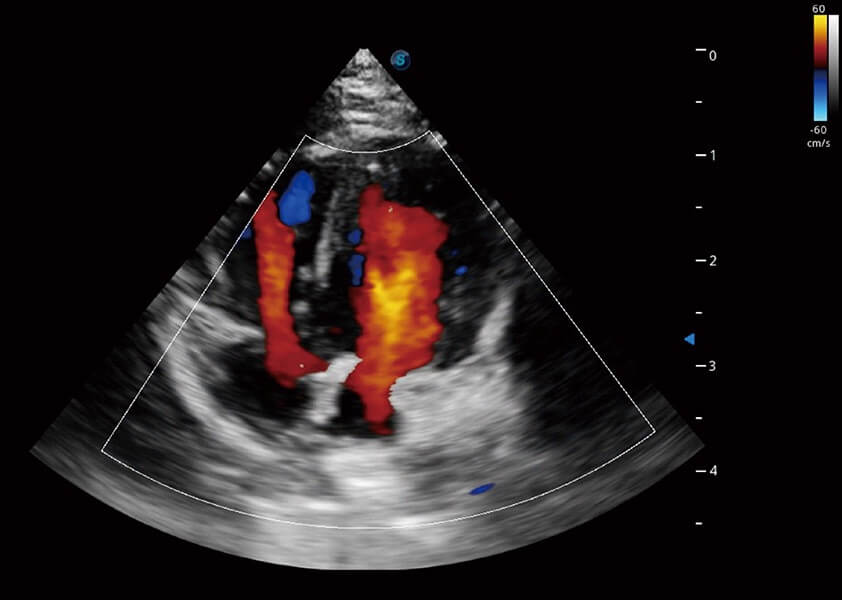

(犬)四腔心血流

ProPet 60 配备了丰富的心脏探头群、先进的成像技术和专业的心脏测量工具,可帮助动物医生为不同体型和生理结构的动物提供心脏和心肌功能的全面评估。